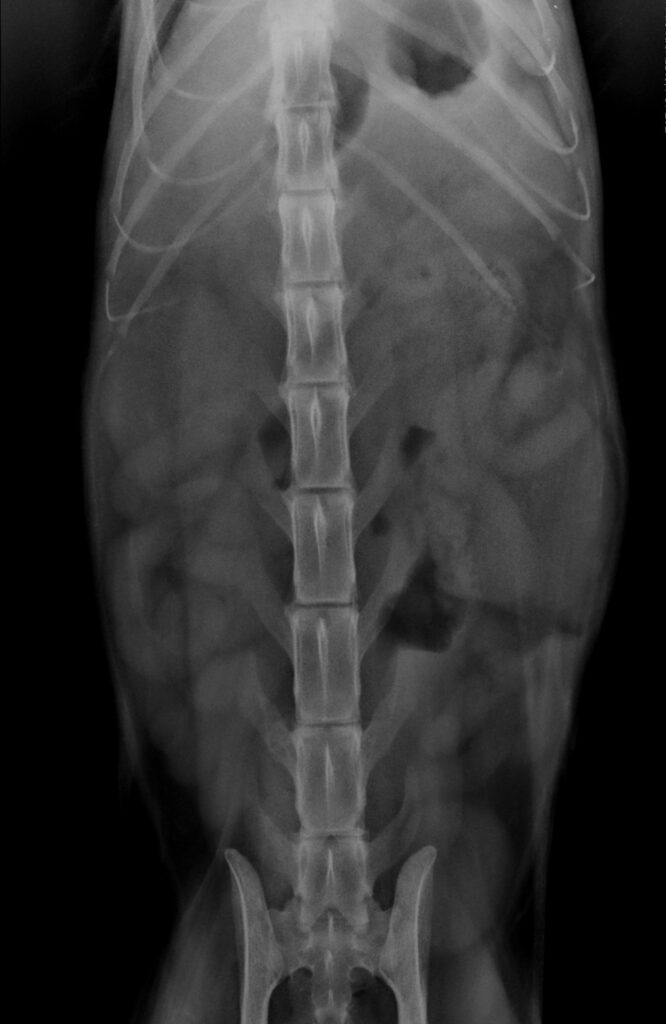

Se llevaron a cabo otras pruebas complementarias consistentes en radiografías y ecografía de abdomen.

Las radiografías de abdomen revelaron un aumento de radiodensidad de la silueta renal izquierda como hallazgos más significativos.